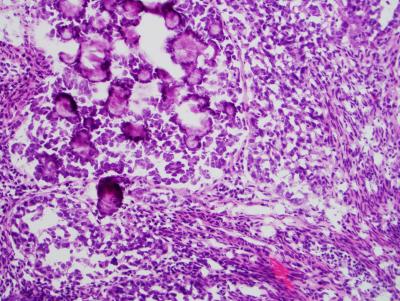

Researchers have identified several genes that are linked to one of the most lethal forms of uterine cancer, serous endometrial cancer. The researchers describe how three of the genes found in the study are frequently altered in the disease, suggesting that the genes drive the development of tumors. The findings appear in the Oct. 28, 2012, advance online issue of Nature Genetics . The team was led by researchers from the National Human Genome Research Institute (NHGRI), part of the National Institutes of Health.

Each of its three major subtypes — endometrioid, serous and clear-cell —is caused by a different constellation of genetic alterations and has a different prognosis. Endometrioid tumors make up about 80 percent of diagnosed tumors. Surgery often is a complete cure for women with the endometrioid subtype, since doctors usually diagnose these cases at an early stage.

Compared to other subtypes, the 2 to 10 percent of uterine cancers that comprise the serous subtype do not respond well to therapies. The five-year survival rate for serous endometrial cancer is 45 percent, compared to 65 percent for clear-cell and 91 percent for endometrioid subtypes. Serous and clear-cell endometrial tumor subtypes are clinically aggressive and quickly advance beyond the uterus.

Dr. Bell's team focused on the rarer, more aggressive forms of endometrial cancer. They began their study by examining serous tumor tissue and matched normal tissue from 13 patients. National Cancer Institute and Massachusetts General Hospital pathologists processed the 26 tissue samples, which subsequently underwent whole-exome sequencing at the NIH Intramural Sequencing Center.